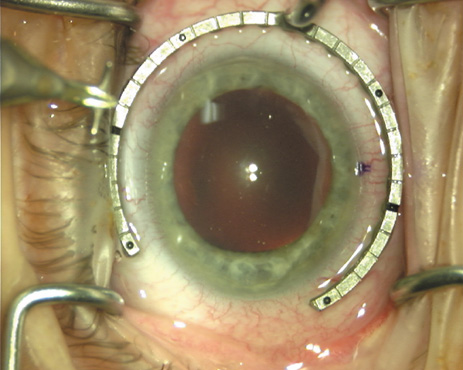

Case 3 is a 48-year-old bilateral hyperope who presented for a refractive surgical consultation. The refraction in his left eye was found to be +3.25 +1.75 × 85. Keratometry was somewhat flat but confirmed WTR cylinder as did corneal topography. Based upon the patient's age, refraction, and somewhat shallow anterior chambers, the decision was made to proceed with a refractive lens exchange. The NAPA nomogram called for LRIs of 55 to 60 degrees with intraoperative pachymetry. Intraoperative keratoscopy confirmed the steep 85-degree meridian (Figs. 2029).

Fig. 20. Keratoscopy, after lifting of the speculum to relieve induced pressure and distortion of the corneal mires, confirms the steep axis of 85 degrees.